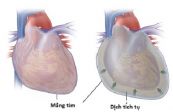

Tràn dịch màng tim là tình trạng có quá nhiều dịch tích tụ ở giữa hai lớp của màng ngoài tim, có khả năng gây chèn ép tim và đe dọa tính mạng. Hãy cùng eLib để tìm hiểu thêm về căn bệnh này nhé!